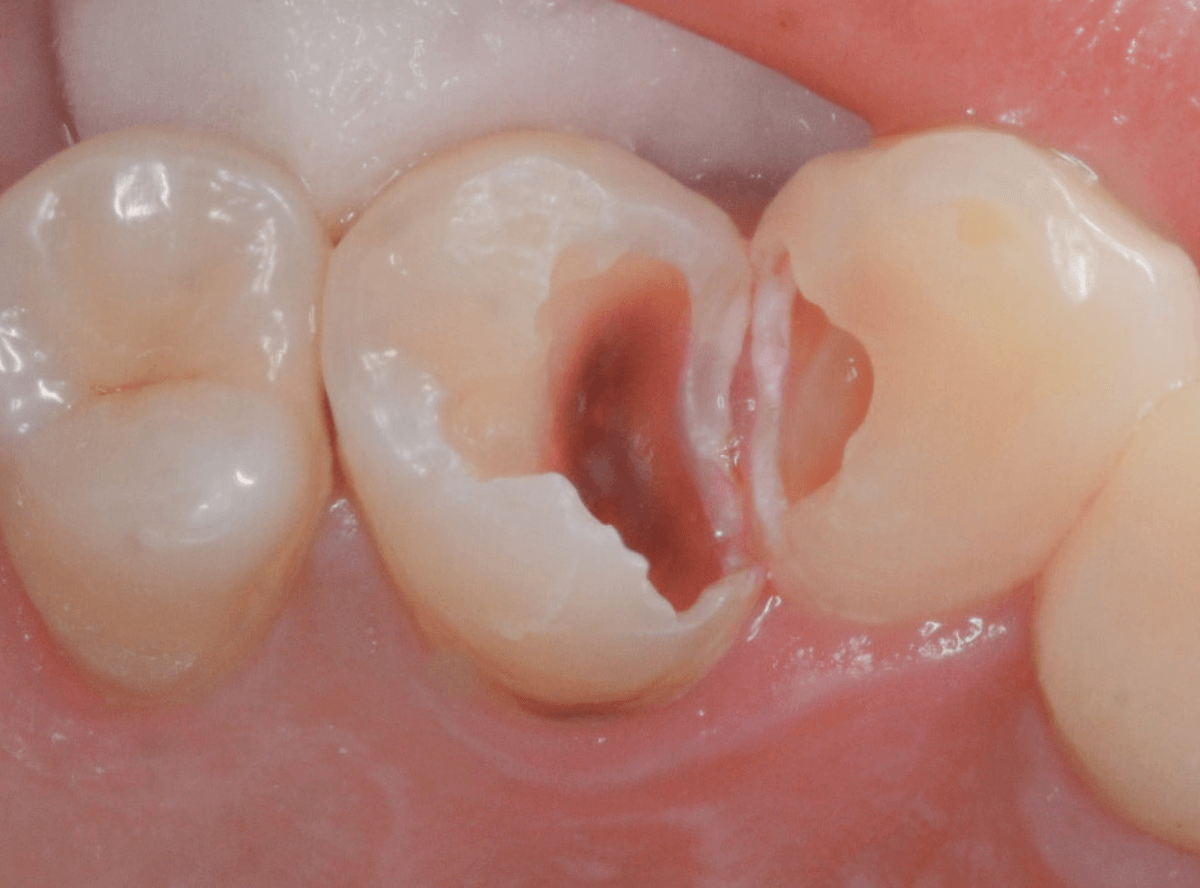

Case.22 痛みはないけど、歯のすきまから大きな虫歯

上の小臼歯の間が虫歯になっていた患者さんです。

症状はありませんし、見た目からも虫歯があるかはわかりませんでした。

レントゲン写真で確認します。

赤い線が虫歯、青い線が歯の神経です。

歯のすきまから両側に虫歯が大きく広がっているのが確認できます。

治療を開始します。

少し削ると、中からすぐに虫歯が出てきました。